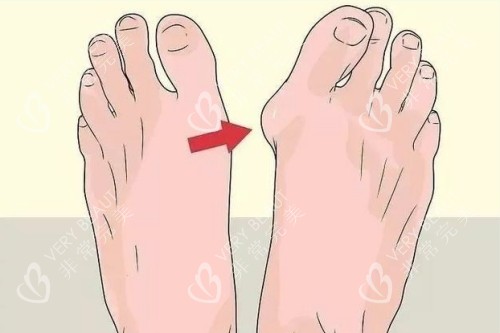

在追求美丽与健康的道路上,大脚骨问题成为了许多人的困扰。它不仅影响足部美观,还可能引发疼痛与功能障碍。北京广济医院凭借其在大脚骨治疗领域的卓然表现,成为了众多患者的信赖之选。下面,让我们深入了解一下这家医院。

医院重视患者的个体差异,针对不同病情和体质的患者,制定个性化的治疗方案。对于轻度外翻患者,可能建议采用支具调整结合改善训练;而中重度患者则需通过手术矫正骨骼和软组织平衡。这种个性化的治疗方案满足了患者的需求,确保了手术结果的满意度和自然度。